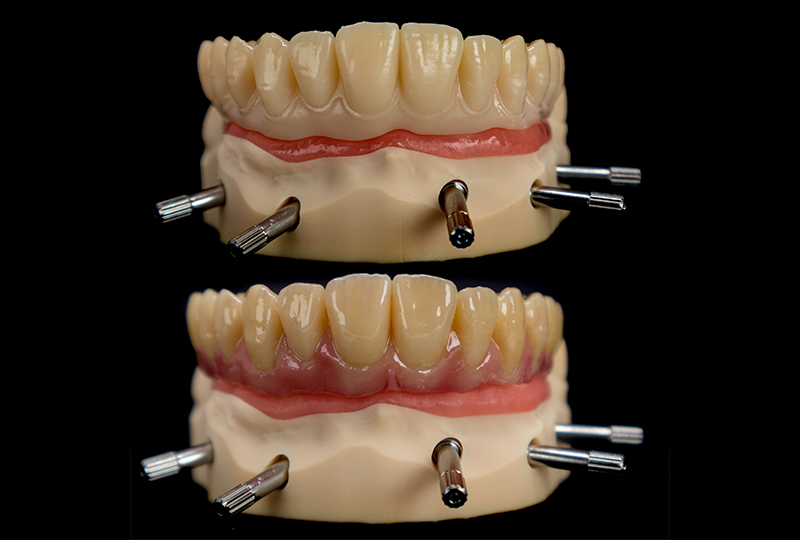

La struttura estetica in resina BEGO Triniq viene stampata sempre con la stampante Dental Makers LB4K 2.0. La parte "bianca" viene finita con Shofu lite art e glasata, avendo già caratteristiche estetiche idonee, mentre la parte rosa viene caratterizzata con uno strato in composito Shofu Ceramage (Figure 19, 20 e 21).

Stampa della parte estetica definitiva e caratterizzazione tramite composito

Fig. 20, 21

La barra, fresata in materiale metal-free su fresatore a 5 assi, sarà la trave portante della protesi, assemblata e incollata sul modello stampato (Figura 22). L’accoppiamento tra barra e impianti è affidato a TiBase Custom-Interface (IPD Dental Group / AbutmentCompatibili.com). I TiBase sono incollati con OT-Cem (Rhein83) sulla chiave in gesso di validazione finale per garantire la totale passività della struttura sia in laboratorio che sul paziente (Figure 23, 24). La consegna e la validazione finale avvengono con il serraggio della vite più distale e l’osservazione clinica della staticita’ struttura, seguita dal classico check radiologico mirato. (Figure 25, 26 e 27).

Barra fresata in 5 assi, verifica della passività su modello stampato con Tibase

Conclusione delle fasi di laboratorio su modello stampato

Fig. 25